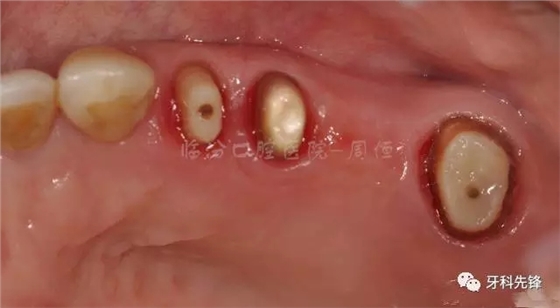

圖4拆除原修復(fù)體牙列照

640.webp (5).jpg